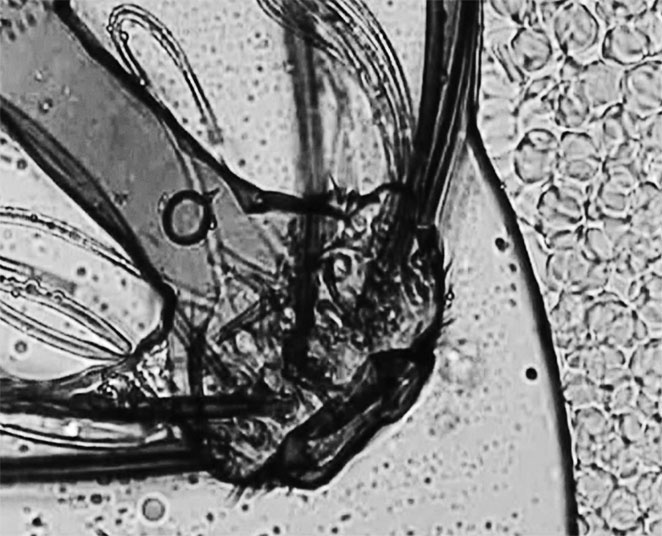

Давайте посмотрим на «неопознанного паразита» при большом увеличении и сравним с личинкой паразита, которую мы уже видели. ![]() Антенна-4 Что бросается в глаза? Личинка – гладкая, гибкая, без каких-либо выступов и узлов, приспособленная для передвижения в стесненных условиях. А «неопознанный паразит» весь покрыт длинными выростами, которые наверняка будут затруднять его продвижение. Кроме того, у личинки можно без труда определить, где вход в кишечный тракт (рот), а где из него выход (не рот). У волосатого чудища ни первое, ни второе найти не получается. Да и размеры просто гигантские: такое не то что в капилляры – не в каждую вену поместится. Итак, как и в примере с личинкой паразита, мы имеем дело со срежиссированным артефактом. Нечто таких размеров и очертаний через прокол в подушечке пальца не сможет выбраться ни при каких условиях, то есть наблюдаемое в микропрепарате привнесено извне. И в данном случае можно точно установить, что это и откуда оно взялось. Помните, мы говорили о том, что гемосканирование обычно проходит в не приспособленных для этого помещениях, грязных с точки зрения требований к клинической лаборатории? Так вот, «неопознанный паразит» попал в каплю крови из воздуха, и на самом деле это обломок хитиновой антенны комара-звонца. На фотографии с сайта Университета Мичигана очень хорошо видно сходство. ![]() Комар-звонец Кристаллы В нашем организме действительно могут образовываться кристаллы. Чаще всего в моче, но и в крови они иногда встречаются. Например, игольчатые кристаллы уратов (солей мочевой кислоты) при подагре. Их можно увидеть после определенной подготовки (фиксация, окраска) [62] препарата крови, однако при гемосканировании их почему-то обнаруживают и в живой капле, причем в очень интересном виде. ![]() Мочевая кислота Ну да, некая игольчатость присутствует, края острые, похожие на осколки… Постойте, но ведь это и есть осколки! Присмотритесь, отлично видно, что стекло треснуло в центре от давления сверху. Так происходит, когда неопытные лаборанты или студенты слишком быстро выкручивают винт, приближающий объектив микроскопа к предметному столику. Линза сначала упирается в лежащее сверху препарата тонкое покровное стекло, а затем раздавливает его с характерным грустным хрустом. Кроме того, попадаются особенно сильные уникумы, умудряющиеся сломать таким манером и куда более толстое предметное стекло, на которое наносится капля крови или образец другой ткани. Впрочем, в атласе встречаются и более экзотические примеры. Вот, скажем, кристаллы ортофосфорной кислоты. ![]() Ортофосфорная кислота Этим микропрепаратом рекомендуется пугать подростков, любящих пепси или кока-колу. Не знаю, как такое зрелище действует на неокрепшие детские умы, но у человека, имеющего большой опыт работы с микроскопом и обладающего познаниями в клинической лабораторной диагностике, оно вызывает лишь смех. Во-первых, ортофосфорная кислота прекрасно растворяется в воде [63], и с 1952 года, которым датирован указанный в сноске справочник, ровным счетом ничего не изменилось. Во-вторых, кристаллизуются ее полугидраты, и итоговые кристаллы получаются белого цвета, а не черного. В-третьих, для кристаллизации при температуре тела требуется настолько высокая насыщенность раствора [64], что это должна быть кровь Чужого, а не человека. В-четвертых, если присмотреться, можно заметить, что черное пятно находится на переднем плане, то есть не внутри крови, а как бы перед ней. И это ощущение абсолютно правильное. С подобными «кляксами» сталкивались многие лаборанты: это самая обычная грязь на линзе объектива. С «кристаллами сахара», которые, по мнению составителей атласа, запечатлены на следующей фотографии, история примерно та же. ![]() Кристаллы сахара Во-первых, «сахара» в крови нет. Основной простой углевод нашего организма – моносахарид глюкоза. И авторам якобы медицинского издания неплохо бы это знать. Во-вторых, глюкоза в той концентрации, в которой она присутствует в крови, и при температуре тела кристаллизоваться не может [65], ей запрещают это делать законы химии и физики. Вспомните, когда засахаривается мед или варенье. Приблизительно столько же «сахара» должно быть и в крови. Холестерин Вообще-то в соответствии с химической номенклатурой этот жирный спирт положено называть холестеролом, но, чтобы вы, уважаемые читатели, окончательно не запутались, воспользуемся устоявшимся в русском языке, хотя и некорректным термином. Вот так, по мнению авторов атласа, выглядит под микроскопом холестерин. ![]() Холестерин |